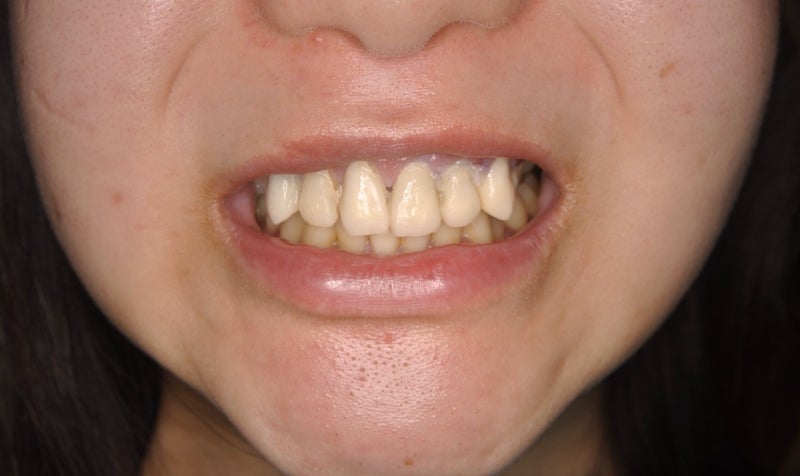

<初診時口腔内>

▶︎上の歯全てを土台の状態に削り、仮の歯が入っていますがおおよそ1時間という短時間で

勢いよく (乱暴に?) 削られたとの事でした。

その後削られた歯全てに激痛が出てしまい生活に支障が出るほど困られており

今回はついに痛みに限界が現われて心配になり、知人のご紹介により当院に来院されました。

審美不良の仮歯による歯肉の炎症、そして1時間で8本の歯を一気に削るという無理な治療によって

歯の神経にも歯髄炎という病気を起こしている状態でした。